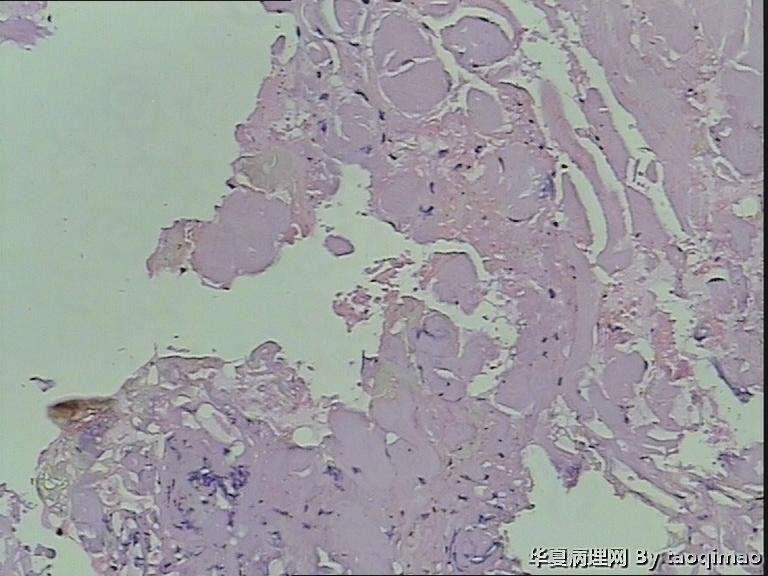

胸壁肿物

结节性筋膜炎+神经节样细胞+肌肉浸润=增生性肌炎。

粗略看了下,对软组织病变不是很在行,初步印象是增生性肌炎,几个图像里小血管内皮肿胀,周围炎细胞浸润,结合临床除外血管炎或者自身免疫相关疾病。

男,54岁,右侧胸壁肿物发现1月余,取材:灰白色不规则组织一块2*1.7*0.5cm,剖面实性灰白色,质韧。